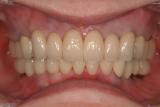

審美歯科治療 | ||

| 40代女性の患者さんです。再生療法などの様々な技術を用いて審美的に仕上げました。が最も大切なものは「咬み合わせ」です。見た目だけではいけません。(SHILLA SYSTEM使用) | ![]() |

【治療前】 |

【治療後】 |